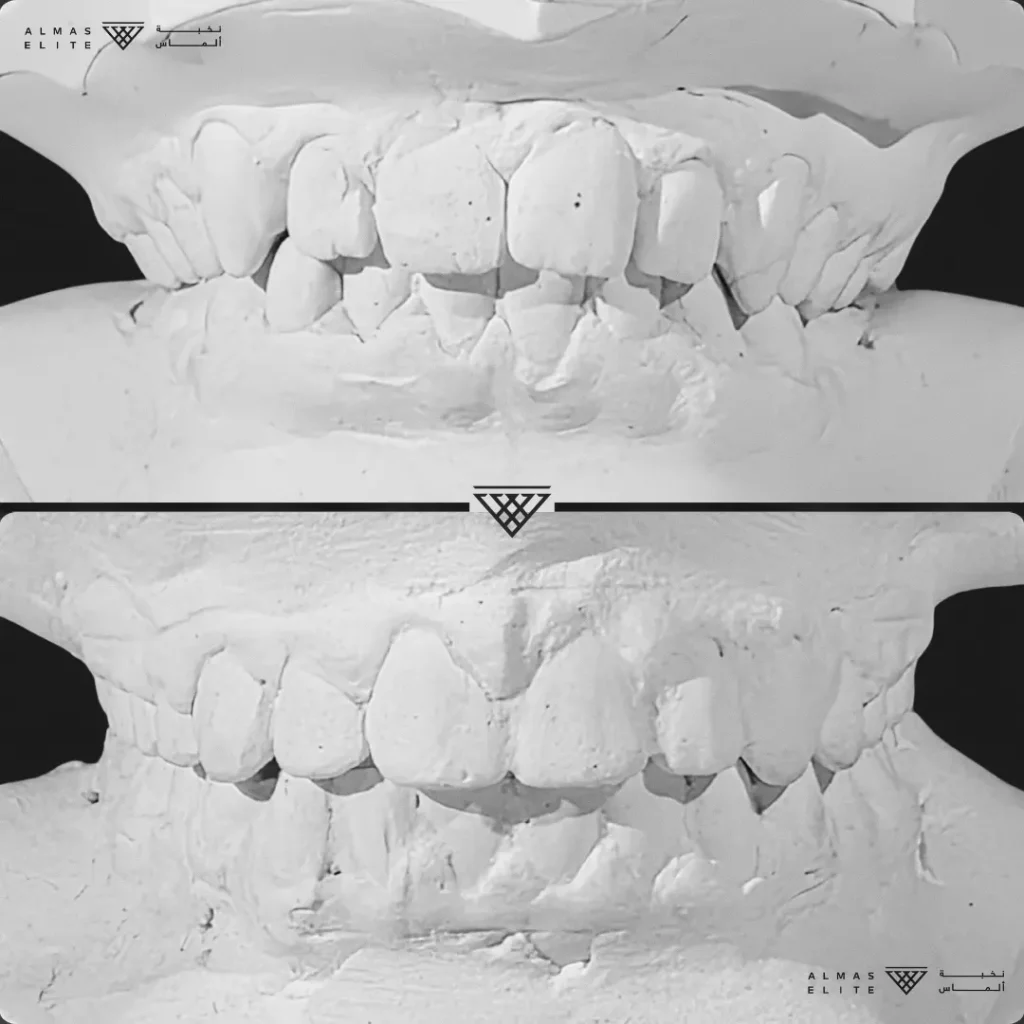

٢) التقييم والتشخيص الشامل

يشمل صور الأشعة والتحليل الرقمي للأسنان والفكين للوصول إلى تشخيص دقيق.

٣) وضع خطة علاجية مخصصة

تتضمن نوع الجهاز الأنسب، المدة المتوقعة، وتكلفة العلاج، مع شرح واضح لما يمكن توقعه أثناء رحلة التقويم.

- تشخيص دقيق يشمل الأشعة والتحليل الرقمي للأسنان والفكين.